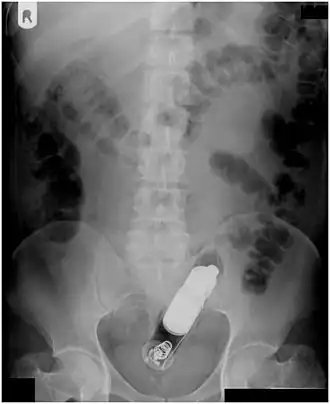

| Radiograph of a male abdomen with a vibrator inside the rectum | |

Usually, several radiological images are recorded in order to pinpoint the precise place and depth of the foreign body. This is usually done by X-ray. Foreign bodies made from low-contrast material (e.g. plastics) may necessitate medical ultrasound or a CT scan.[29] Magnetic resonance imaging is contraindicated, especially if the foreign body is unknown. Foreign rectal bodies may penetrate deep into the colon, in certain circumstances up to the right colic flexure.[10]